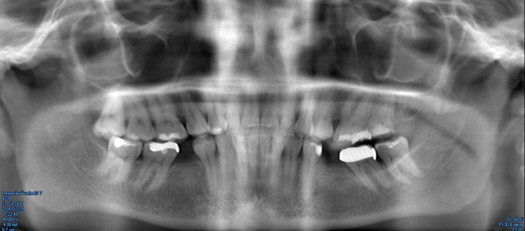

Fig 10. Preoperative panoramic radiograph.

Figure 10

Figure 10 through Figure 13 show the preoperative x-ray and the sequence of beginning with healed sites through the surgical placement of the implants. The implants were protected by an Essix-style wound-protection removable retainer for approximately 12 weeks. After the integration phase, the implants and the natural dentition were prepared using traditional crown-and-bridge high-speed diamond and zirconia cutting burs to remove decay and existing restorative materials, to complete and refine the natural-tooth structures to receive full-crown coverage, and to prepare and refine gingival margins of the zirconia implants where needed.